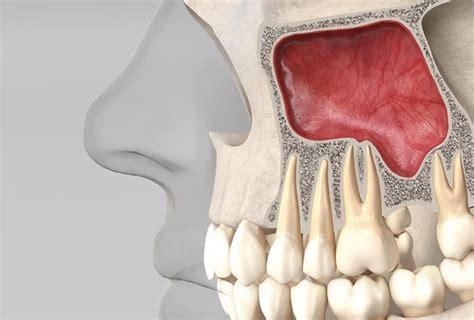

- Elevación del Seno Maxilar: Otro de los procedimientos que aplicamos en los casos de falta de hueso y encía es la elevación del seno maxilar. Esta intervención nos permite rellenar con hueso esta zona para poder colocar implantes de mayor longitud. Cuando se han extraído los molares superiores, el hueso de la cresta se reabsorbe y la cavidad sinusal se expande, de modo que finalmente el hueso que separa la cavidad sinusal y la cavidad oral es muy delgado. Los implantes dentales no se pueden colocar en huesos tan delgados y en estos casos hay que realizar una elevación de los senos nasales. El seno se eleva empujando suavemente hacia arriba la membrana que recubre el seno y empaquetando material de injerto óseo en el espacio donde estaba la cavidad del seno. Indicada en casos de falta de hueso en el maxilar superior posterior.